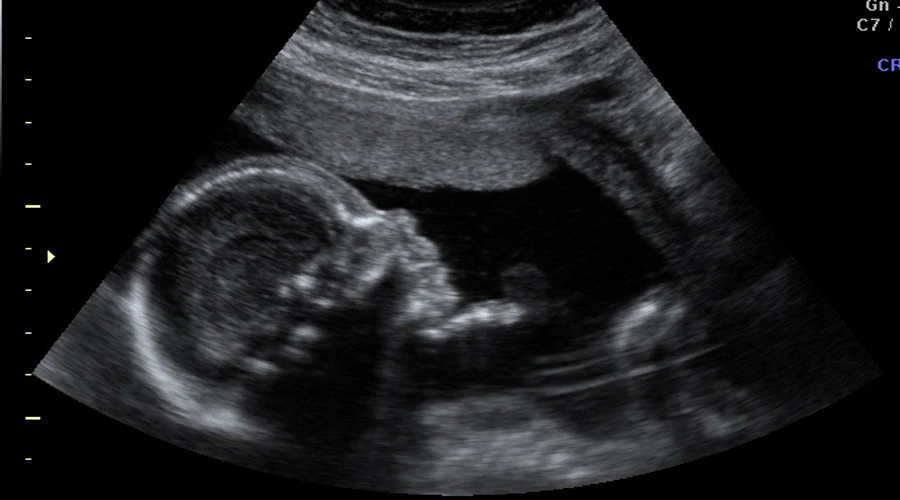

Desde 2012, en Uruguay el aborto está despenalizado hasta las 12 semanas de embarazo y, según cifras del 2015 del Ministerio de Salud Pública, se practica en promedio unos 780 abortos por mes.